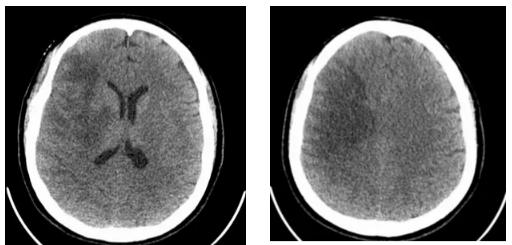

2025年10月11日,42岁的女性患者因突发左侧肢体无力、呕吐、意识障碍等症状被紧急送医。医院立即开启绿色通道,迅速完成头颅MRI检查,并在黄金时间窗内实施了阿替普酶静脉溶栓治疗。次日,患者病情急剧恶化,出现严重脑水肿并形成脑疝。虽曾考虑转往西宁进一步救治,但因路途遥远、转运风险巨大,加之患者家属对医院充满信任,最终决定留在囊谦县人民医院继续治疗。

在医疗条件相对有限的高原县城,救治团队克服困难,对患者进行了不间断的严密监测,连续追踪头颅CT影像变化。经过数个日夜的坚守和精心治疗,患者的病情终于出现了转机。至10月22日复查显示,致命的脑疝得到缓解,脑水肿范围显著缩小,患者成功度过了最危险的阶段,病情逐步稳定下来。